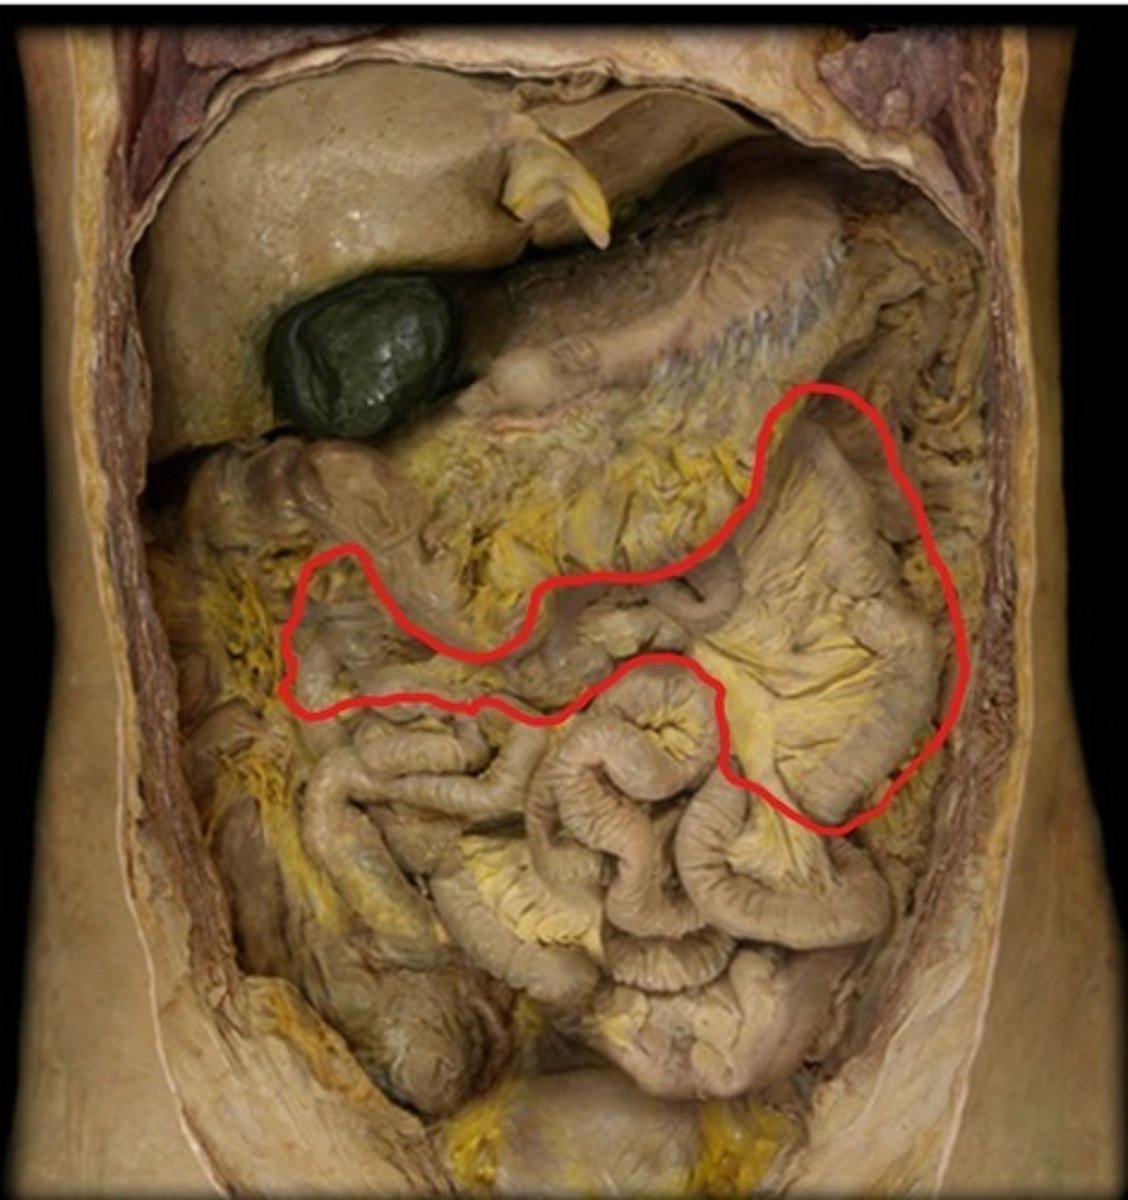

Jejunum

Transverse colon